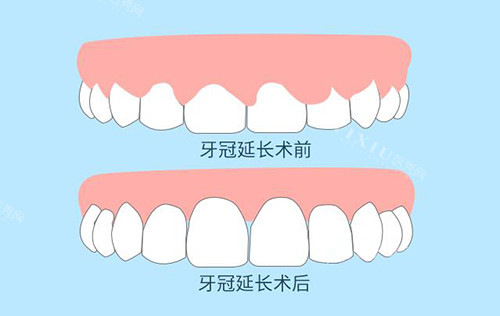

牙冠延长术:比较准调整,重塑比例

牙冠延长术是解决龈笑露龈问题的关键一步。它就像是技艺娴熟的雕刻师,通过手术的方式,比较准地去除部分牙龈组织和骨组织,从而暴露出更多的牙冠结构。

这一过程需要医生具备高超的技术和丰富的经验,因为要精细控制去除的组织量,既要达到改善牙龈暴露比例的目的,又不能损伤牙齿的根基和周围的健康组织。手术完成后,牙齿的外观会得到显著改善,原本被过多牙龈遮挡的牙冠得以充分展现,为后续的贴面修复打下良好的基础。